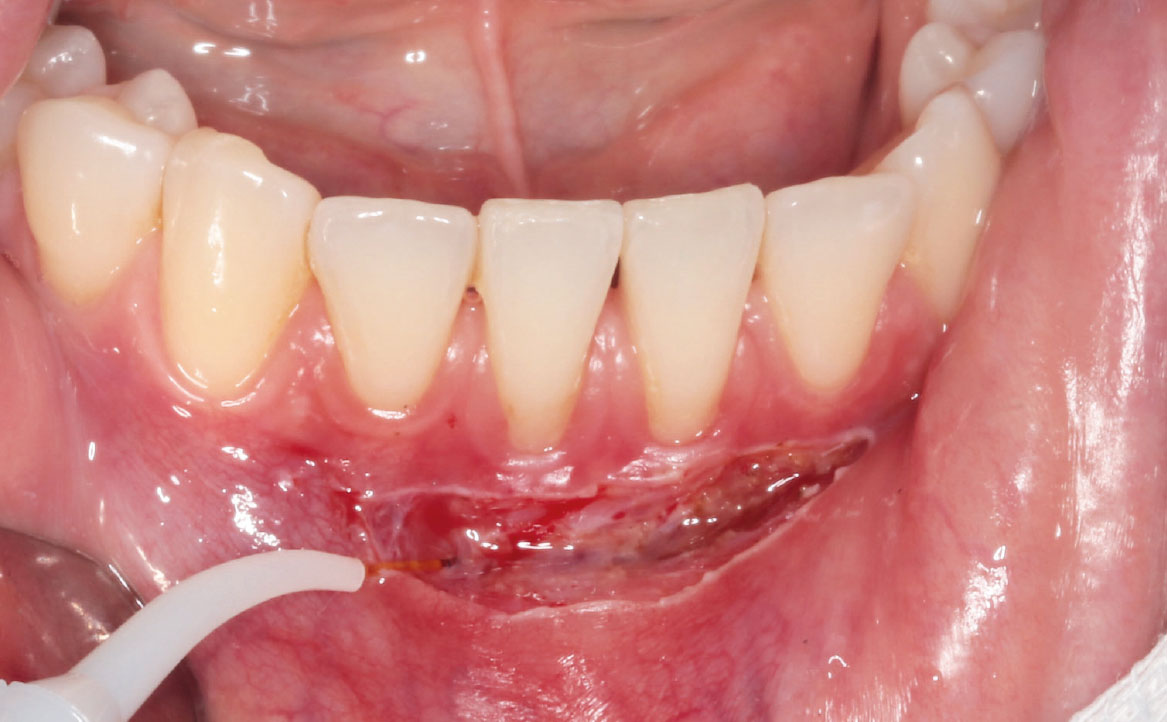

Previa anestesia loco-regionale plessica con lidocaina, è stata eseguita un’incisione parallela rispetto alla cresta alveolare e scollamento della mucosa mediante un laser neodymium yttrium aluminum garnet laser (Nd:YAG, 1064nm, 3.75W, 75Hz) (fig. 4-5).